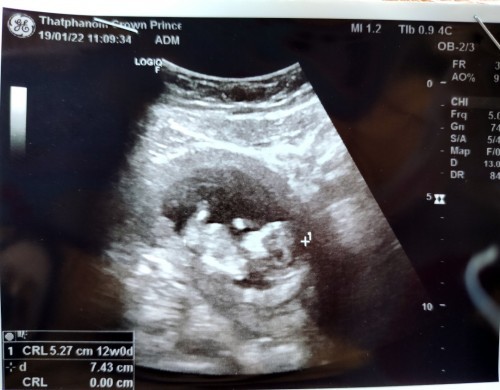

พึ่งไปซาวมาวันนี้หมอบอกน้อง12สัปดาห์แล้วค่ะ ดิ้นเก่งมากๆยกขายกแขนดุ๊กดิ๊กๆโชว์ป้าหมอเลย ดีใจและตื่นเต้นมากๆ อยากถามแม่ๆรู้เพศน้องกี่สัปดาห์กันค่ะ เดือนที่แล้วน้องยังเป็นก้อนเล็กๆอยู่เลยมาเดือนนี้น้องโตขึ้นเยอะมากแม่กินน้ำมันมะพร้าววันละ2ช้อนโต๊ะทุกวันผสมกับนมหรือน้ำเต้าหู้ในตอนเช้าค่ะ #ทีมท้องแรกค่ะ #ขอคำแนะนำหน่อยค่ะ